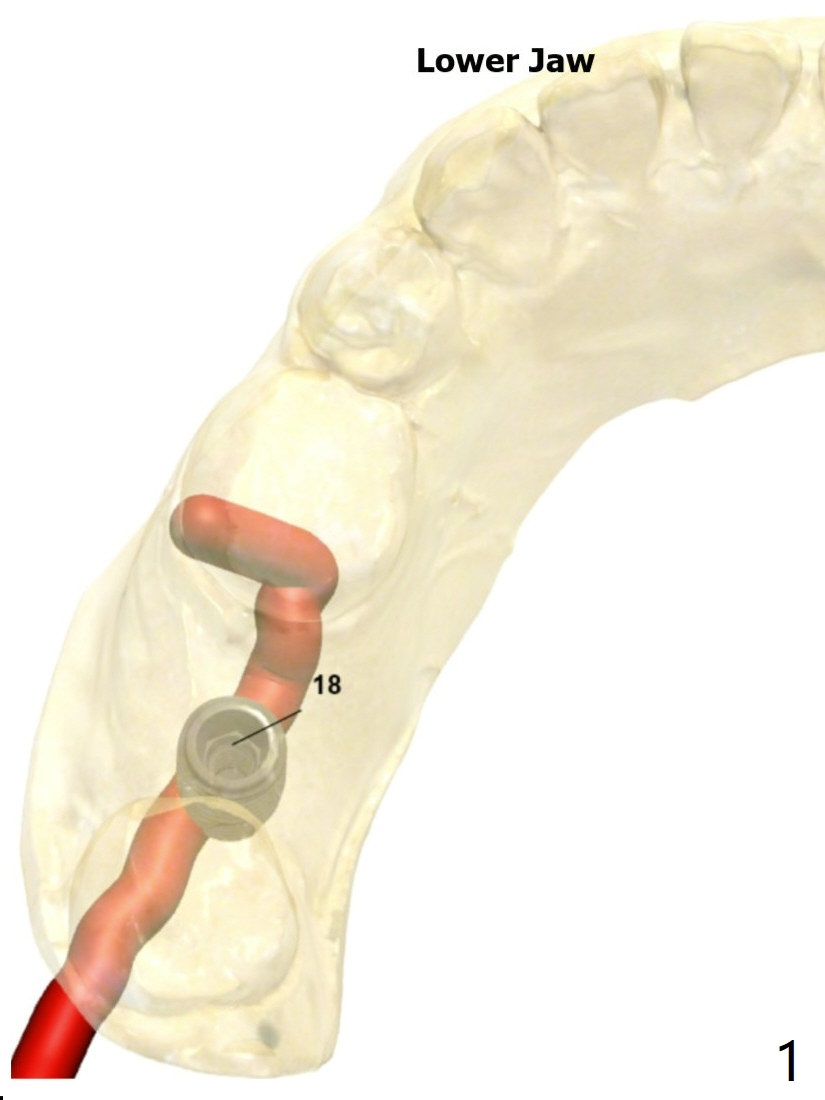

A 25-year-old woman. For sinus lift, 9 mm offset will be used from now on so that DIO sinus approach kit can be applied. Get ready water lift.

Upper

Lower Molar

Immediate Implant,

Trajectory II